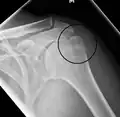

Proximal humerus fracture

Fractures of the humerus are classified based on the location of the fracture and then by the type of fracture. There are three locations that humerus fractures occur: at the proximal location, which is the top of the humerus near the shoulder, in the middle, which is at the shaft of the humerus, and the distal location, which is the bottom of the humerus near the elbow.[9] Proximal fractures are classified into one of four types of fractures based on the displacement of the greater tubercle, the lesser tubercle, the surgical neck, and the anatomical neck, which are the four parts of the proximal humerus, with fracture displacement being defined as at least one centimeter of separation or an angulation greater than 45 degrees. One-part fractures involve no displacement of any parts of the humerus, two-part fractures have one part displaced relative to the other three; three-part fractures have two displaced fragments, and four-part fractures have all fragments displaced from each other.[13][14][3] Fractures of the humerus shaft are subdivided into transverse fractures, spiral fractures, "butterfly" fractures, which are a combination of transverse and spiral fractures, and pathological fractures, which are fractures caused by medical conditions.[12] Distal fractures are split between supracondylar fractures, which are transverse fractures above the two condyles at the bottom of the humerus, and intercondylar fractures, which involve a T- or Y-shaped fracture that splits the condyles.[7]